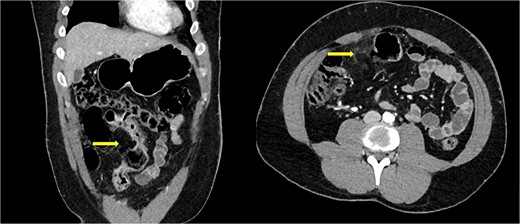

Initial pan-computed tomography (CT) reported ‘no acute injury in the head, neck, chest, abdomen and pelvis’. Due to concern of perforation from examination, we requested a second review of the CT. The addended CT reported ‘bowel wall thickening in the terminal 20 cm length of ileum in keeping with known Crohn’s disease in this region but there appears to be an acute complication of possible evolving perforation of a focal area of distal ileum ~17 cm proximal to the ileocecal junction. There is an out-pouching of the gas in this region through the transmural inflammation and there is mild surrounding mesenteric inflammation’ (Fig. 1).

Abdominal computed tomography of coronal and axial cuts showing bowel perforation (arrow).